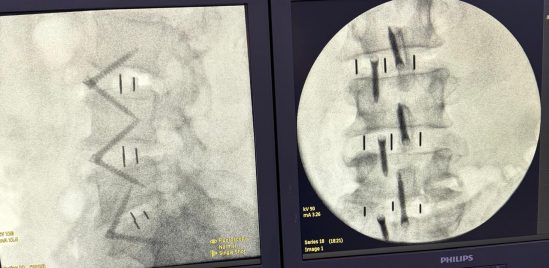

Cirurgia com a técnica ALIF no Beda (Divulgação)

Imagem de coluna de um paciente submetido à técnica